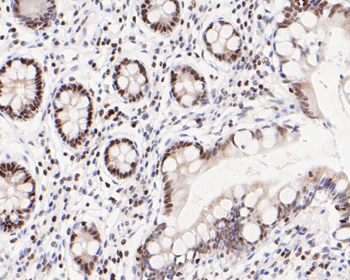

100 μl, 50 μl, 200 μl - HSC70 Mouse Monoclonal Antibody [orb704174]Featured

IF, IHC-Fr, IHC-P, WB

Human, Mouse, Rat

Mouse, Rat

Mouse

Monoclonal

Unconjugated

100 μl, 50 μl, 200 μl - ATF4 Recombinant Rabbit Monoclonal Antibody [orb704304]Featured